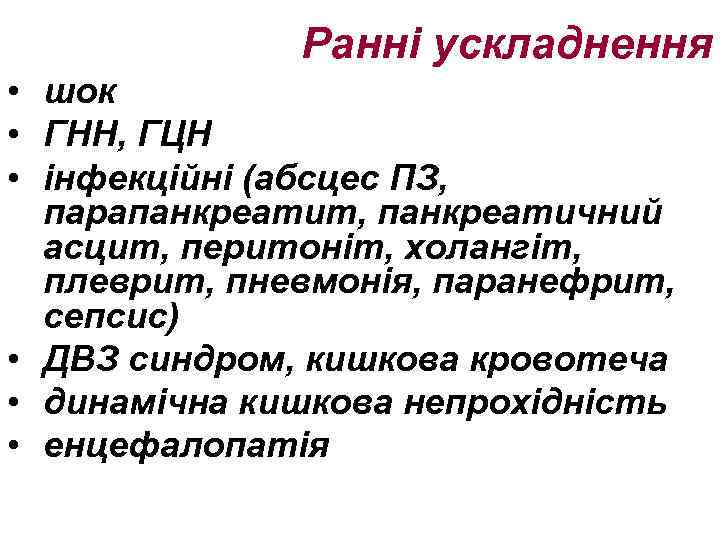

Ранні ускладнення • шок • ГНН, ГЦН • інфекційні (абсцес ПЗ, парапанкреатит, панкреатичний асцит, перитоніт, холангіт, плеврит, пневмонія, паранефрит, сепсис) • ДВЗ синдром, кишкова кровотеча • динамічна кишкова непрохідність • енцефалопатія

Ранні ускладнення • шок • ГНН, ГЦН • інфекційні (абсцес ПЗ, парапанкреатит, панкреатичний асцит, перитоніт, холангіт, плеврит, пневмонія, паранефрит, сепсис) • ДВЗ синдром, кишкова кровотеча • динамічна кишкова непрохідність • енцефалопатія